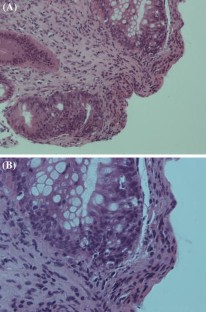

The histopathological mimics of inflammatory bowel disease: a critical appraisal

The pathological diagnosis of inflammatory bowel disease (IBD) is often difficult because biopsy material may not contain pathognomonic features, making distinction between Crohn’s disease, ulcerative colitis and other forms of colitides a truly challenging exercise. The problem is further complicated as several diseases frequently mimic the histological changes seen in IBD. Successful diagnosis is reliant on careful clinicopathological correlation and recognising potential pitfalls. This is best achieved in a multidisciplinary team setting when the full clinical history, endoscopic findings, radiology and relevant serology and microbiology are available. In this review, we present an up-to-date evaluation of the histopathological mimics of IBD.

Fig. 2